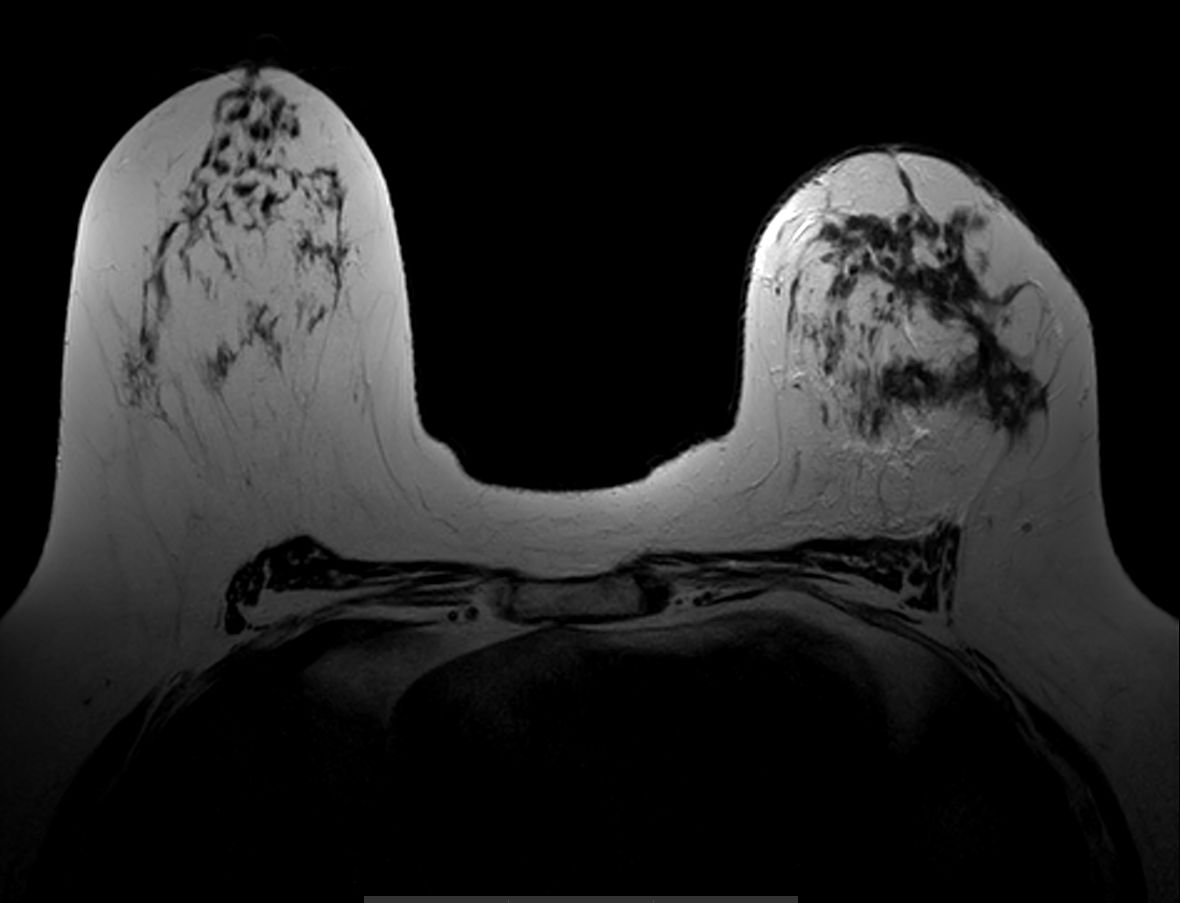

Axial T1w FFE

Axial T2w TSE

Axial T1w FFE mDIXON

Axial dynamic T1w FFE

Axial dynamic T1w FFE (subtraction)

Axial T1w FFE mDIXON (post-gado)

Axial T1w FFE mDIXON (post-gado) (MIP)